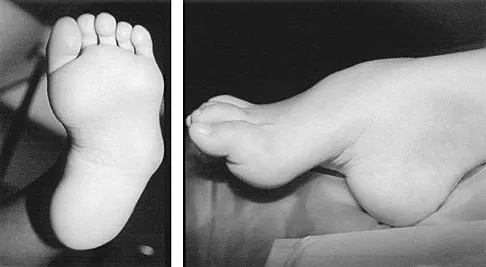

What is the most common surgical cause of the foot deformity shown in Figure 9?

Explanation